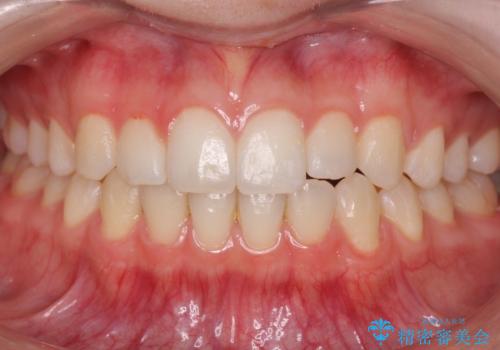

[ 前歯のねじれ・がたつき ] マウスピース矯正

![[ 前歯のねじれ・がたつき ] マウスピース矯正の症例 治療前](https://seimitsushinbi.jp/wp/wp-content/uploads/2024/02/4007c6479f6bce11863dcdd32ed5e39b-500x350.jpg?v=1708502552)

![[ 前歯のねじれ・がたつき ] マウスピース矯正の症例 治療後](https://seimitsushinbi.jp/wp/wp-content/uploads/2024/02/e7a01485e4f4dd0da04705fde4cc34cc-500x350.jpg?v=1708502585)